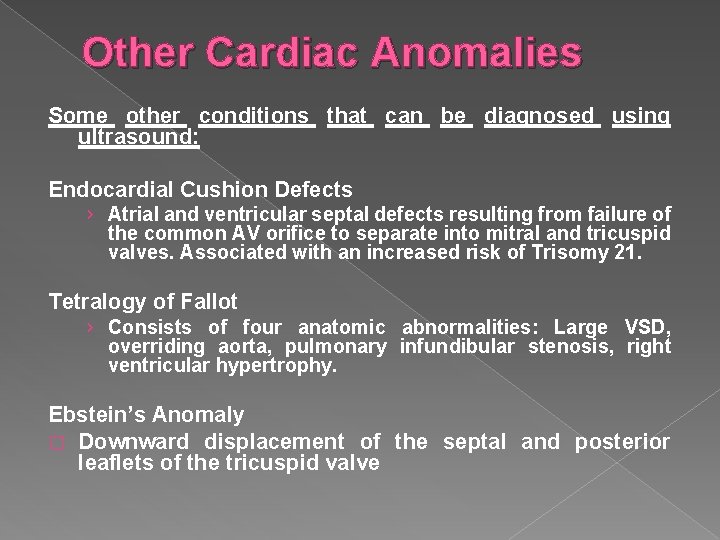

Other Cardiac Anomalies Some other conditions that can be diagnosed using ultrasound: Endocardial Cushion Defects › Atrial and ventricular septal defects resulting from failure of the common AV orifice to separate into mitral and tricuspid valves. Associated with an increased risk of Trisomy 21. Tetralogy of Fallot › Consists of four anatomic abnormalities: Large VSD, overriding aorta, pulmonary infundibular stenosis, right ventricular hypertrophy. Ebstein’s Anomaly � Downward displacement of the septal and posterior leaflets of the tricuspid valve

� Endocardial cushion defect is also called atrioventricular septal defect (AVSD). AVSD involves problems with the structure of the heart. The heart normally has 2 upper chambers (atria) and 2 lower chambers (ventricles). A normal heart also has 2 heart valves (the tricuspid and mitral valves) that separate the upper and lower chambers.

� In AVSD, there may be a large hole in the center of the heart where the wall (septum) joins the upper and lower chambers of the heart. The tricuspid and mitral valves may not be separate. Instead, there can be one large valve between the upper and lower chambers of the heart (common atrioventricular valve). The large opening in the center of the heart allows the oxygen-rich (red) and the oxygen-poor (blue) blood to mix. The heart pumps blood in a way that is not efficient and becomes enlarged.

An AVSD is the most common congenital heart defect found in children with Down's Syndrome, accounting for 50% of the total. � In its complete form there is a hole in the wall between the top chambers (atria) and a hole in the wall between the bottom chambers (ventricles), and one common valve between the two atria and the two ventricles. In the partial forms there may not be a hole between the bottom chambers (ventricles) or the mitral and tricuspid valves may not be joined together, but either or both may leak, known as valve incompetence. �